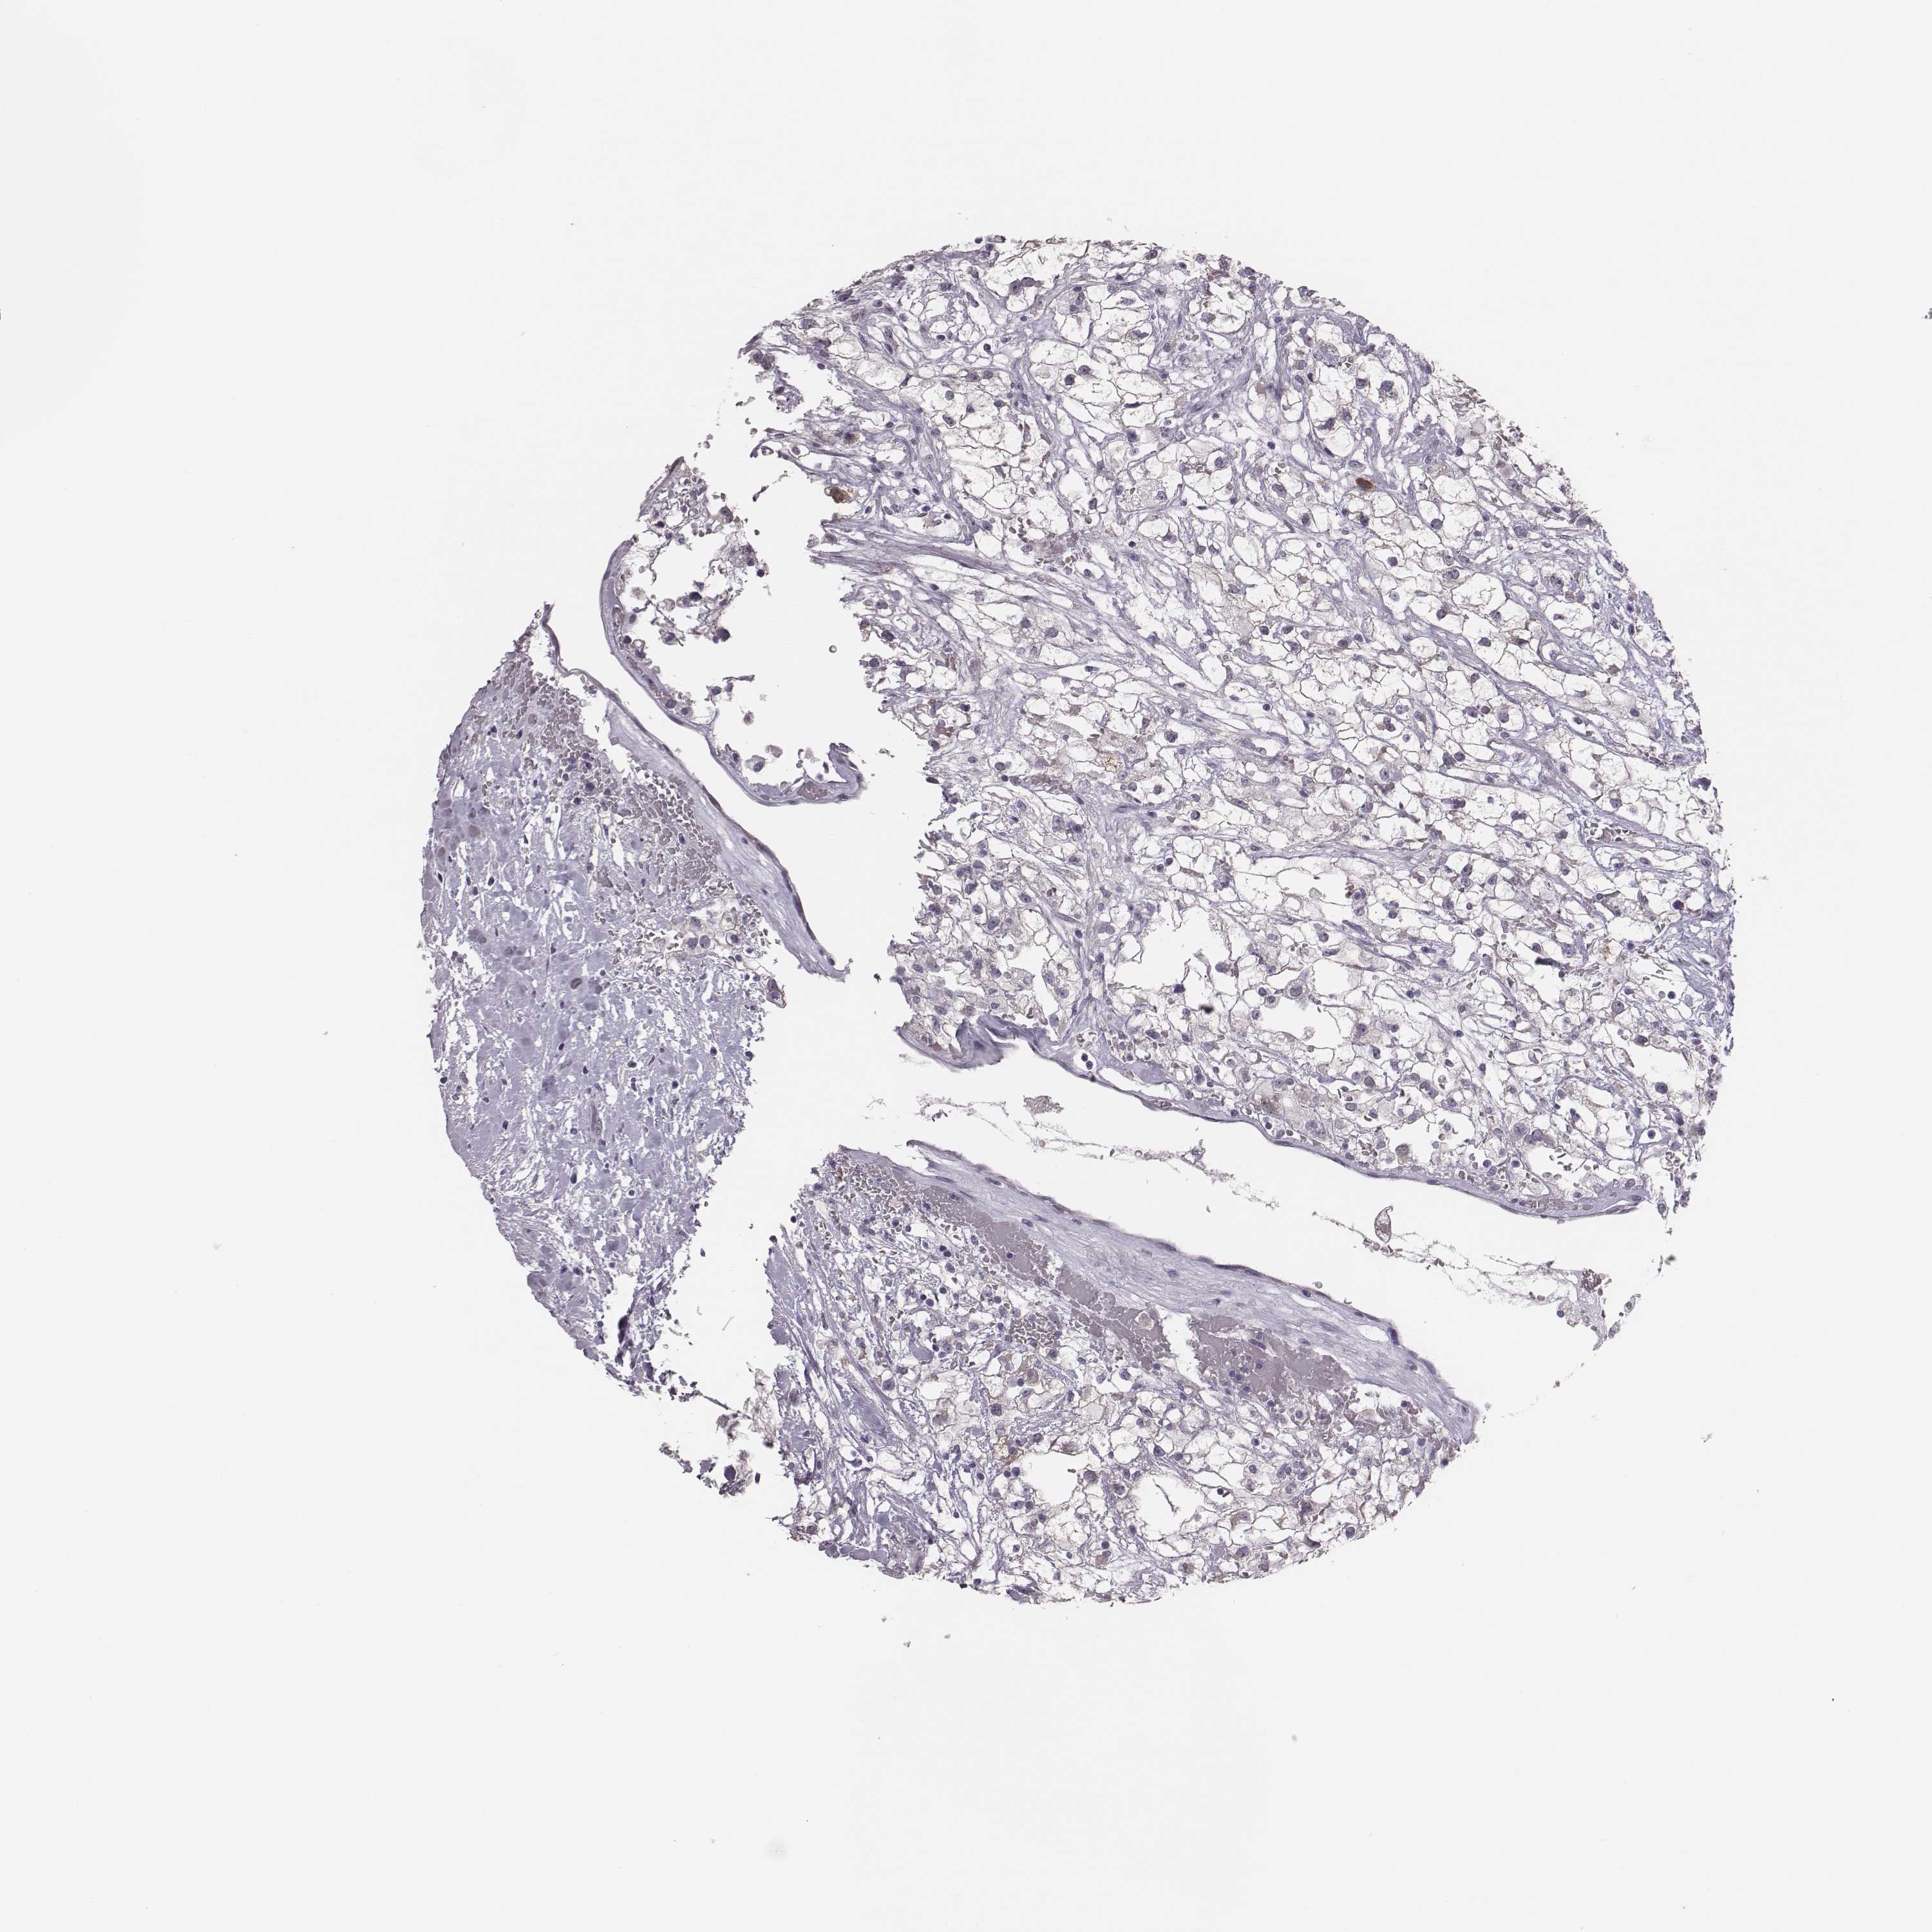

KIDNEY RENAL CLEAR CELL CARCINOMA (VALIDATION) - Interactive survival scatter ploti

The Survival Scatter plot shows the clinical status (i.e. dead or alive) for all individuals in the patient cohort, based on the same data that underlies the corresponding Kaplan-Meier plots. Patients that are alive at last time for follow-up are shown in blue and patients who have died during the study are shown in red.

PBK is potential prognostic, high expression is unfavorable in Kidney Renal Clear Cell Carcinoma (validation)

: 3.22

Average pTPM 3.2

Number of samples 100